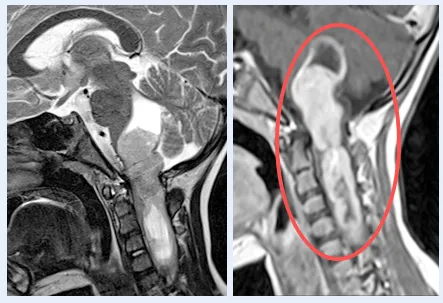

虽然是间变型少突胶质细胞瘤,但海迪在手术+化疗的综合治疗下,随访11年,她长大了,身体状态良好,连为她手术的巴教授也十分高兴。

术后MRI